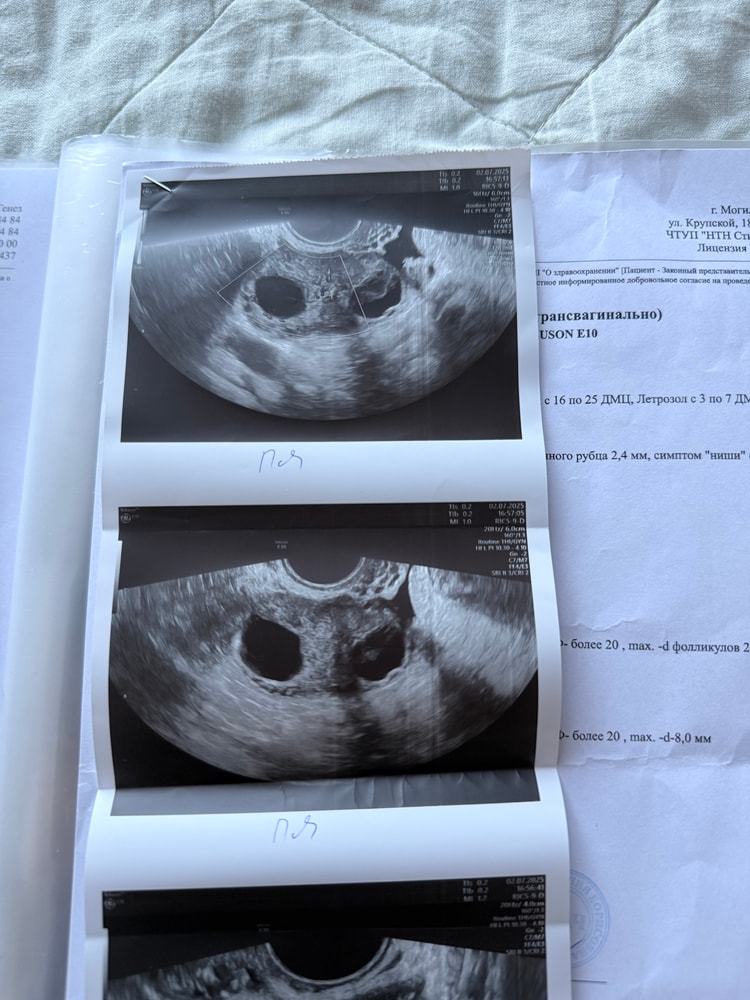

УЗИ на 14 ДЦ, в ПЯ фолликул 14.1 мм (доминантный). Эндометрий 5 мм.

УЗИ на 16 ДЦ, в ПЯ фолликул по верхнему полюсу жидкостное включение, размер фолликула 18,6 мм. Миометрий и эндометрий не изменились.

Сегодня 25 ДЦ, картина такая